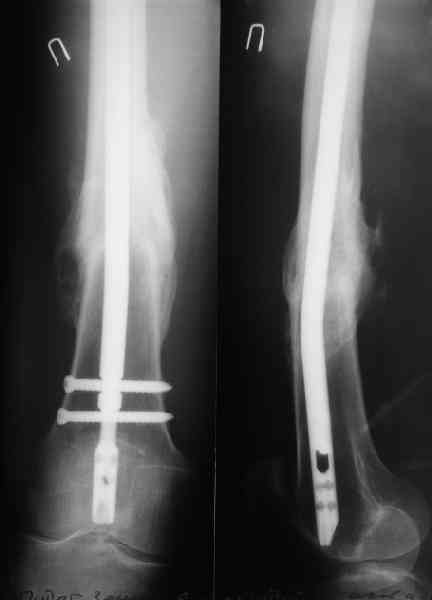

В приложении как раз видна эволюция использововшихся у нас большеберцовых гвоздей. Первый - дизайн как у UTN, второй - разнесены 45 градусные отверстия (зачем их вообще изначально так нелепо на одном уровне сделалм???), третий - убрано сиавшее лишним статическое отверстие, Herzog's bend перемещен более проксимально.